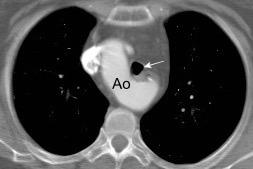

“Draped aorta”.

Indica rotura aórtica reciente. Se manifiesta por una pared aórtica posterior o el contacto con el borde lateral vertebral borrados por la hemorragia.

A. Yudin, Metaphorical

Rotura aneurisma de Aorta descendente.

Dolor. (10 días antes: "Rotura inminente”)